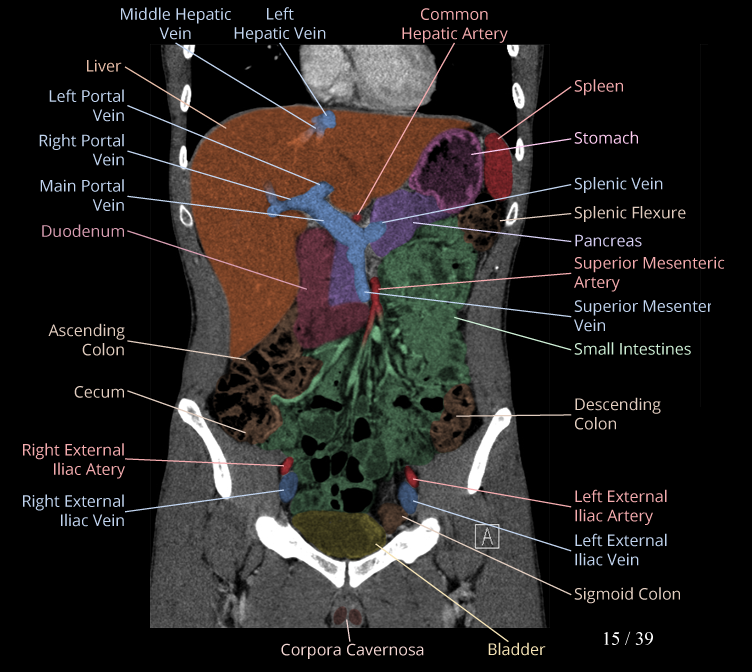

Body

Covers abdominal CT anatomy.